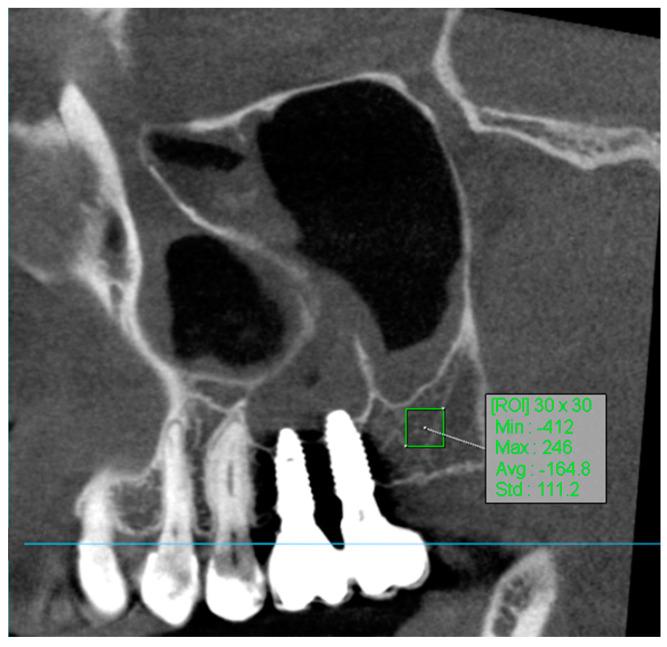

Peri-implantitis is a serious complication in dental implantology that, if left untreated, may lead to implant loss and systemic diseases. Effective regeneration of bone defects resulting from peri-implantitis is crucial to maintaining the functionality of dental implants. The study aimed to compare the effectiveness of fine-particle dentin and Bio-Oss in the reconstruction of bone defects caused by peri-implantitis. The study included a comprehensive radiological assessment of changes in bone density over time. Bone density was assessed using Hounsfield Units (HUs) as a measure of bone attenuation, with radiological assessments performed at 8- and 12-week intervals during the healing process. The study included participants ranging in age from 30 to 65 years. Fifty-seven patients were divided into three groups: 22 patients received small-particle dentin, 15 received Bio-Oss, and 20 controls without bone substitute material. The fine-dentin group showed a 20% increase in bone density after 8 weeks ( < 0.05), while the Bio-Oss group showed a 15% increase after 12 weeks ( < 0.05). The control group showed minimal changes in bone density (5% after 12 weeks), which was not statistically significant. Clinical evaluations showed 95% successful integration in the fine dentin group, 85% in the Bio-Oss group, and 70% in the control group. The fine-dentin group showed a 20% increase in bone density after 8 weeks ( < 0.05), while the Bio-Oss group showed a 15% increase after 12 weeks ( < 0.05). The control group showed minimal changes in bone density (5% after 12 weeks), which was not statistically significant. Clinical evaluations showed 95% successful integration in the fine-dentin group, 85% in the Bio-Oss group, and 70% in the control group. : Both fine-particle dentin and Bio-Oss significantly improved bone density compared to the control group. Fine-particle dentin is suitable for immediate bone regeneration due to its rapid initial regeneration, while Bio-Oss provides long-term support, ideal for maintaining implant stability over a longer period of time. The results highlight the importance of selecting appropriate bone replacement materials depending on the clinical scenario to improve patient outcomes after dental implant placement.

种植体周围炎是牙种植学中的一种严重并发症,若不治疗,可能导致种植体脱落和全身性疾病。有效修复种植体周围炎导致的骨缺损对于维持牙种植体的功能至关重要。本研究旨在比较细颗粒牙本质和Bio-Oss在修复种植体周围炎所致骨缺损方面的有效性。该研究包括对骨密度随时间变化的全面影像学评估。使用亨氏单位(HUs)评估骨密度,作为骨衰减的指标,在愈合过程中每隔8周和12周进行影像学评估。该研究纳入了年龄在30至65岁之间的参与者。57名患者被分为三组:22名患者接受小颗粒牙本质,15名接受Bio-Oss,20名作为未使用骨替代材料的对照组。细颗粒牙本质组在8周后骨密度增加了20%(P<0.05),而Bio-Oss组在12周后增加了15%(P<0.05)。对照组骨密度变化极小(12周后为5%),无统计学意义。临床评估显示,细颗粒牙本质组的成功整合率为95%,Bio-Oss组为85%,对照组为70%。细颗粒牙本质组在8周后骨密度增加了20%(P<0.05),而Bio-Oss组在12周后增加了15%(P<0.05)。对照组骨密度变化极小(12周后为5%),无统计学意义。临床评估显示,细颗粒牙本质组的成功整合率为95%,Bio-Oss组为85%,对照组为70%。与对照组相比,细颗粒牙本质和Bio-Oss均显著提高了骨密度。细颗粒牙本质因其快速的初始再生适合即刻骨再生,而Bio-Oss提供长期支持,非常适合在较长时间内维持种植体稳定性。结果突出了根据临床情况选择合适的骨替代材料以改善牙种植术后患者预后的重要性。

Assessment of CBCT gray value in different regions-of-interest and fields-of-view compared to Hounsfield unit.评估不同感兴趣区和视野下的 CBCT 灰度值与亨氏单位的关系。

Dentomaxillofac Radiol. 2023 Nov;52(8):20230187. doi: 10.1259/dmfr.20230187. Epub 2023 Oct 24.